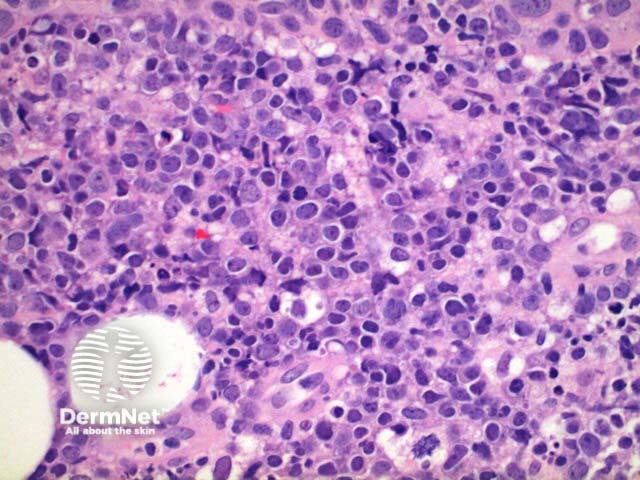

Scanning power view of the histology of primary cutaneous diffuse large B cell lymphoma is of a dense superficial and deep cellular infiltrate (figure 1). Higher power identifies a dense atypical lymphocytic proliferation, which frequently extends into the subcutaneous tissue (figures 2, 3, 4, 5). Areas of crush artefact are common, and while not specific may be a clue to a malignant lymphoid population (figures 2, 3). The lymphocytes are large centroblast-like and immunoblast-like cells with non-cleaved nuclei and prominent nucleoli (figure 6, 7).

Figure 6

Figure 7